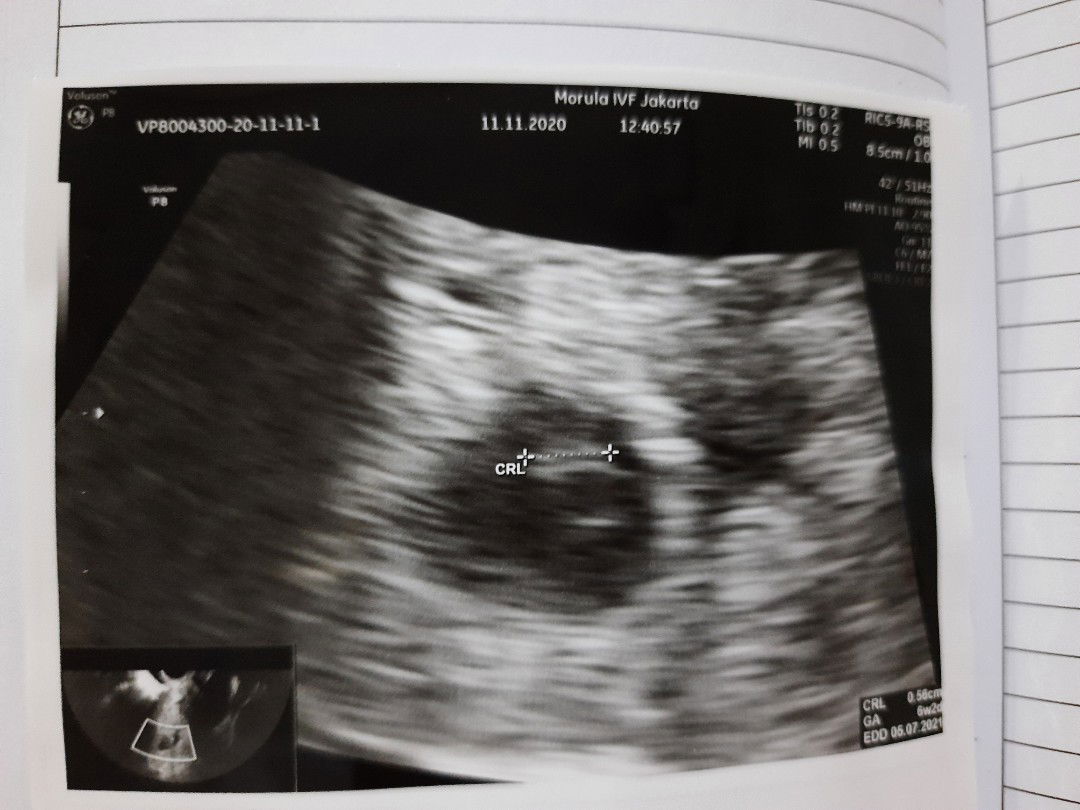

Mau nnya aku udh hamil jln 4 bln,tp kmrn kta Bu bidan udh Kya 5 bln gmna ya ??jadi binggung